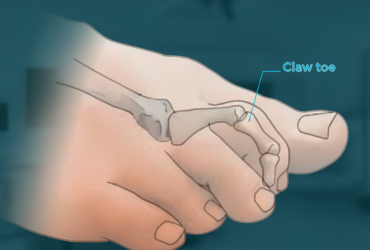

Claw Toe – a deformity where toes bend into a claw-like shape, affecting walking and balance.